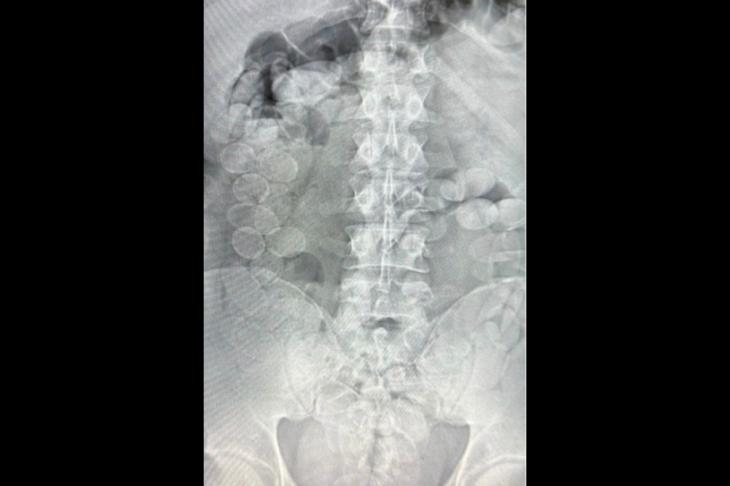

Durante la inspección, un can detector marcó el equipaje de uno de los pasajeros y luego a otro de los ocupantes. Ambos comenzaron a manifestar malestar físico y confesaron que transportaban droga ingerida en cápsulas, por lo que fueron trasladados al hospital local.

Los estudios confirmaron la presencia de los envoltorios en sus organismos. En total, expulsaron 185 cápsulas de cocaína, con un peso superior a los 2,4 kilos y una pureza promedio del 85%. Según la fiscalía, esa cantidad podía traducirse en más de 20 mil dosis.